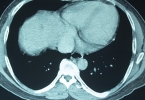

脑梗塞是由脑血管病变引起的血管闭塞,引起局灶性脑缺血引起的脑组织不可逆性损害。急性脑梗塞患者应尽快送往有检查和治疗条件的医院,搬运过程中应注意平卧,保护呼吸顺畅。急性脑梗塞的治疗与患者的个人状况和药物 ...

脑出血呕吐的原因很多,结果脑出血是脑比较严重的疾病。首先,脑出血时,颅内压力增加,颅内压力增加的典型症状是呕吐。其次,脑出血引起刺激性溃疡,消化道出血,此时颅内压上升,容易吐血。症状严重的话,吐血量也 ...